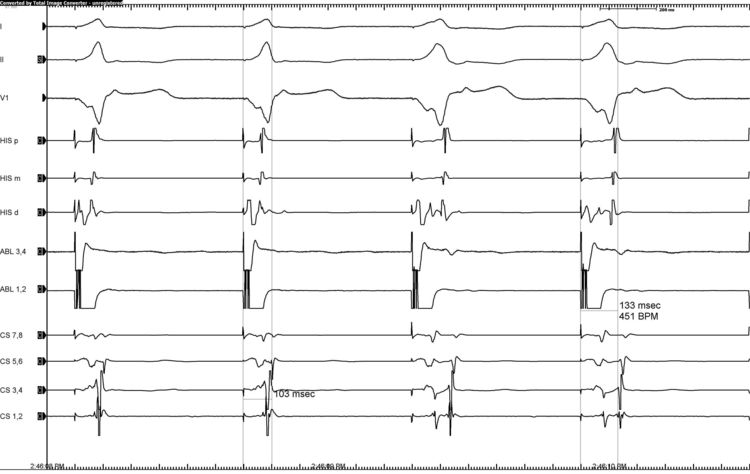

Example of Parahisian Pacing with No Evidence of an Accessory Pathway

• Notice in the 1st and 2nd beats the His is captured resulting in a narrow QRS complex. In the 3rd and 4th beat we lose His capture and only capture the local ventricle resulting in a wider QRS with a retrograde His seen in His distal on the image above. The Stim to A with His capture is 103 ms and the Stim to A without His capture is 133 ms meaning that there is absence of a septal pathway.